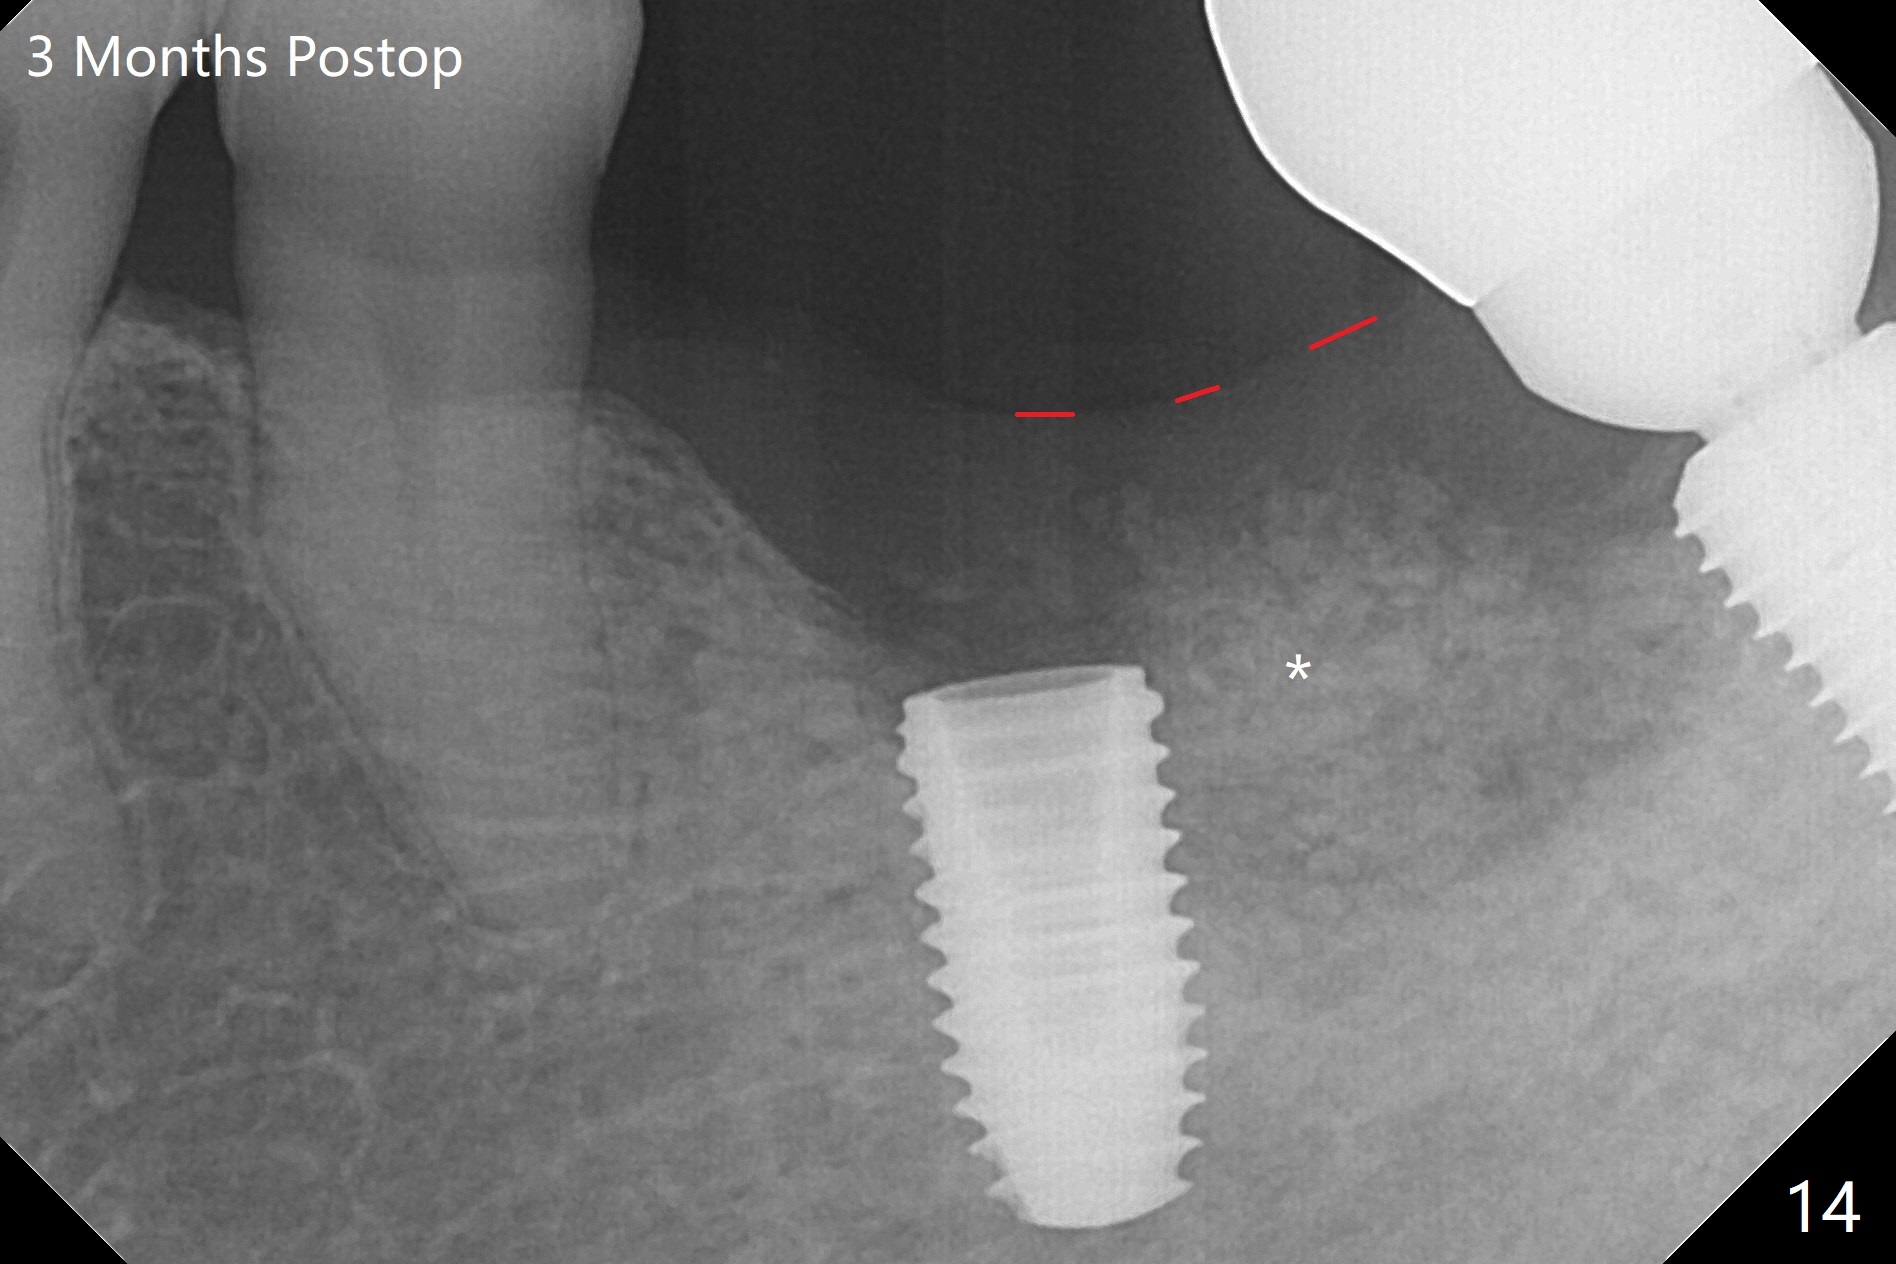

Probably due to severe infection at #19, pain control is difficult. Osteotomy has to be stopped 1.5 mm short of the design. PA taken with a 4.5x10 mm dummy implant does not show the Inferior Alveolar Canal (Fig.1), whereas CT does (Fig.2). With 6 mm clearance, block anesthesia is administered. A 5x10 mm definitive implant is placed with ease (Fig.3). The buccal bony defect is repaired by allograft (Fig.3,4 *), while the soft one by 3 pieces of PRF membrane (Fig.5). The latter is fixed in place by applying setting acrylic as an immediate provisional (Fig.6 P) over the wound, around the abutment (A) and locking into the undercut of the neighboring tooth/implant crown. The patient feels great postop. The gingiva is healthy around the provisional 8 days postop (Fig.7). The patient remains asymptomatic with the healthier gingiva surrounding the simplified provisional 22 days postop, as compared to 8 days postop (Fig.8). The socket heals when the simplified provisional is removed 1.5 months postop (Fig.9-12). The bone graft (Fig.11 ^) seems to have become a part of the regenerated gingiva. The abutment has been dislodged for 2 week (Fig.14 (3 months postop). The bone graft, albeit decreased, is 2 mm subgingival (red dashed line). There is bone distal to the implant 11 months postop (Fig.15 *). There is no bone loss 2 years postop; the UF abutment is completely seated (Fig.16).